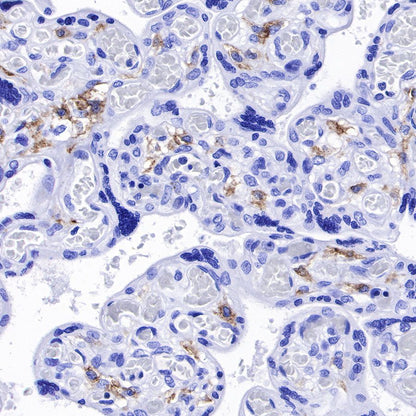

IHC shows positive staining in paraffin-embedded human spleen. Anti-CD169 antibody was used at 1/250 dilution, followed by a HRP Polymer for Mouse & Rabbit IgG (ready to use). Counterstained with hematoxylin. Heat mediated antigen retrieval with Tris/EDTA buffer pH9.0 was performed before commencing with IHC staining protocol.